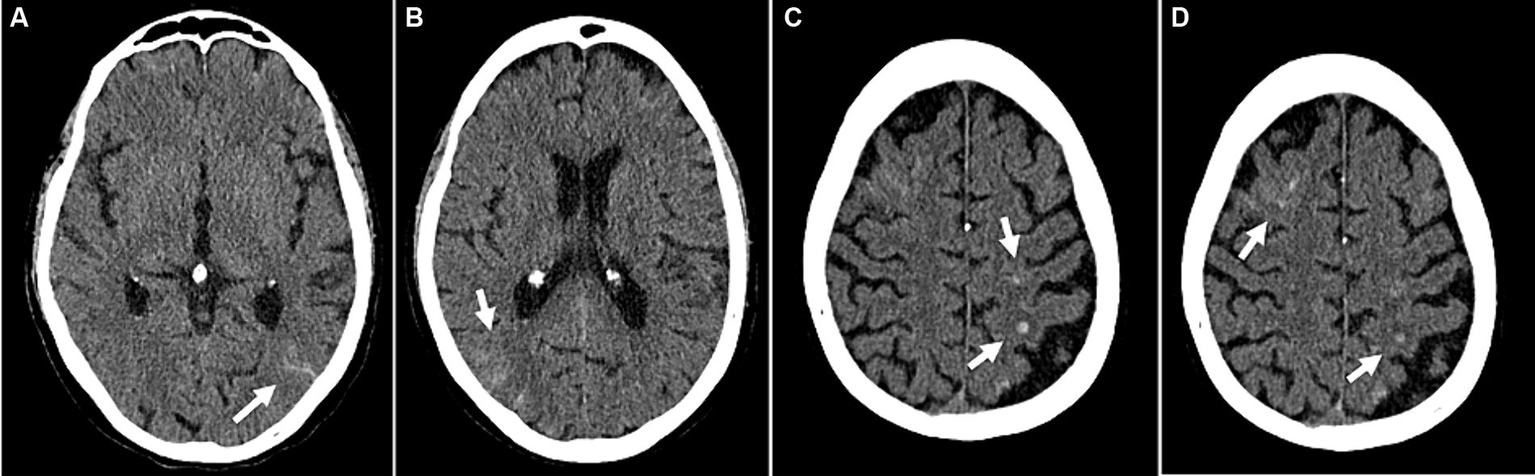

Figure 5

Example of cerebrovascular complications (patient 47): Disseminated small subarachnoid hemorrhages (A,B). Small intracranial hemorrhages in the left parietal and right frontal lobes with adjacent edema (C,D). (A–D) Transversal CT images.

Overall, patients experienced impaired cerebral autoregulation as defined by ORx > 0.3 in 15 ± 9% of total recording time. SARS-CoV-2 patients had 17 ± 9% time with impaired autoregulation while in non SARS-CoV-2 patients this was the case in 13 ± 9% (p = 0.027) as shown in Figure 3. In patients with SARS-CoV-2 infections vs. patients without, if any cerebrovascular complication was identified by cCT pathologies, an even larger percentage of time with dysregulation was observed (19 ± 9 vs. 10 ± 4%, p = 0.032). Cerebral complications in non SARS-CoV-2 patients did not significantly change the amount of time with nonintact autoregulation (10 ± 4 vs. 16 ± 11%, p = 0.26; Figure 4; Table 2). Figure 5 shows an example of cCT images with cerebrovascular complications.